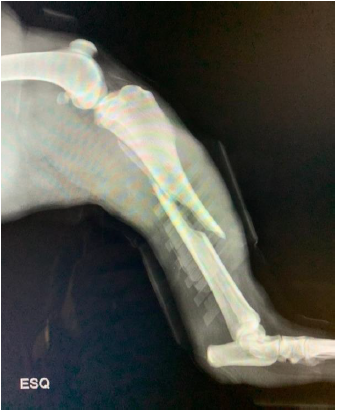

Uma fêmea canina de três anos de idade e com 27 kg foi atropelada ao fugir de pátio onde vivia. Ao retornar para casa, o tutor detectou que o animal não apoiava mais o membro pélvico esquerdo, sendo a paciente levada para consulta veterinária. No exame clínico, não foram detectadas soluções de continuidade na pele, sendo observada dor, crepitação e falta de alinhamento anatômico do referido membro. Após realização da atadura de Robert Jones, foi realizado o exame radiográfico do local afetado em duas incidências perpendiculares entre si e obtidas as imagens abaixo. Considerando a necessidade de encaminhamento para tratamento cirúrgico, assinale a alternativa que contém a classificação e o tratamento cirúrgico indicado para o caso em questão: